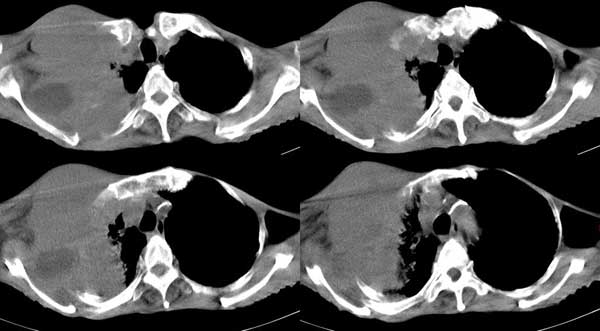

右侧胸廓塌陷。右前上外侧胸壁软组织肿块,其内见有低密度影,肋骨呈溶骨性表现。右肺上叶见大量的间质纤维化表现。右侧膈肌上抬。

肺尖巨大肿块影阴,胸壁受侵肋骨破坏,肿块密度不均且穿破胸壁入皮下,应该是:肺上沟癌;由于肺内有斑片状播散病灶,因此不排除胸壁结核。

我觉得这个人右侧胸部的肿块来源于肋骨或胸壁软组织,从病灶的形态来和最大直径来看,来源于肋骨的可能更大,可以基本定性为恶性。

考虑:1 右侧胸壁恶性肿瘤(多考虑:胸膜间皮瘤)。

2 继发性结核,右结核性胸膜炎伴胸壁结核性感染。

考虑右侧胸壁恶性肿瘤伴右肺癌性淋巴管炎 (肺上沟瘤常有神经方面的症状,结核如此严重无明显结核中毒症状也很少见)

右胸壁恶性肿瘤,以肉瘤可能性大